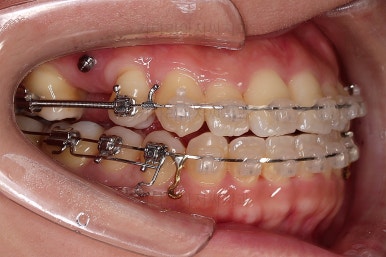

아랫니는 중앙선을 맞추기 위해서 미니스크류를 이용해 한 쪽으로 당기는 중이고요.

이 과정에서 아랫니들이 약간은 뒤로 들어가져서 아랫입술 부위의 돌출감을 아주 약간은 줄일 수 있습니다.

윗니 임플란트 할 자리는 적절히 계속 맞춰줍니다.

중앙선도 점점 맞아지고 있어요.

임플란트 할 공간도 여유롭게 마련이 되었네요.

따라서 교정치료가 100% 끝나기 전에, 임플란트 공간만 마련되면 바로 식립을 하게 됩니다.

임플란트 뿌리 부분이 먼저 식립되었고요.